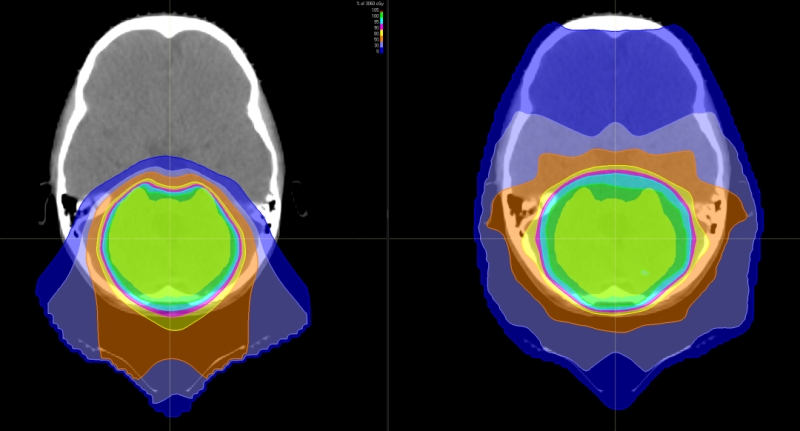

儿童脑瘤的新选择——质子治疗

有研究表明,儿童神经母细胞瘤使用质子治疗的最大效益在于减少脑部正常组织构造的损伤,进而降低长期伤害。质子治疗是一种比其他任何形式的放射治疗更准确,更精确地靶向肿瘤,同时保留健康组织,目前全球最先进的一种放疗技术。通过质子治疗,可以最大限度地避免靶标外部的绝大多数不必要的辐射。

与传统形式的辐射相比,质子束会到达肿瘤内部的精准位置而不是沿着光束离开人体的路径释放大部分辐射剂量。实际上,质子没有肿瘤之外的辐射“退出剂量”,这意味着质子停在肿瘤上,不会继续伤害身体的健康部位。

随着儿童癌症治疗进步,儿童的存活率上升,存活下来的儿童患者日后之生活品质越来越受到关注,质子治疗具备能够减少散射剂量的优势,提升对肿瘤局部的控制,同时由于脑部神经组织多,易受辐射损害。质子治疗因具有布拉格峰的物理特性,使峰值部位对准肿瘤病灶处,发出最高剂量,产生最高峰,达到 杀瘤效果;峰后剂量趋于零,对周边脑组织几乎无影响。对于儿童脑瘤,可以避免有常规化疗引起的听力丧失、认知功能障碍、智力影响等。